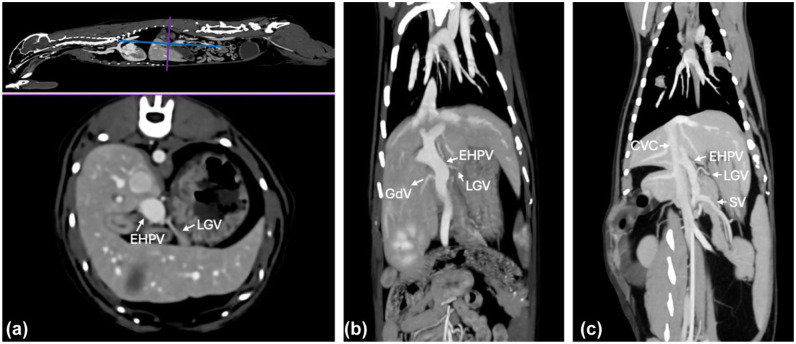

目的在文献中经常提出狗和猫的肝外门静脉(EHPV)的解剖结构相似。然而,在猫的EHPV分支的变化和矛盾已被描述。因此,本研究的目的是描述大群猫中EHPV分支的正常解剖变异。方法对腹部CT血管造影(CTA)进行回顾性、描述性、横断面研究。2020年1月至2024年7月期间接受CTA的猫由三名观察员一致审查。排除血管异常或CTA扫描不能准确评估EHPV或其分支的猫。结果共纳入52张CTA扫描。脾静脉(SV)始终存在于所有猫作为最尾部插入静脉在EHPV。42/52只猫的胃左静脉(LGV)直接进入EHPV,其中36只猫的胃左静脉是进入EHPV最多的颅静脉。在28只直接插入的猫中,LGV的第二个分支进入SV。在8只猫中,单个LGV进入SV,这在狗中很常见。在剩下的两只猫中,LGV没有被确定。在34/52只猫中,胃十二指肠静脉进入EHPV,正如在狗中所描述的那样,而在其余18只猫中,右胃静脉和颅胰十二指肠静脉一起进入EHPV。结论及相关性发现了欧洲人乳头状瘤病毒插入静脉的各种解剖变异。了解EHPV及其分支的正常解剖结构的变化是很重要的,特别是对评估EHPV的复杂病理,如血管异常和EHPV血栓形成。

ObjectivesIt is often suggested in the literature that the anatomy of the extrahepatic portal vein (EHPV) in dogs and cats is similar. Nevertheless, variations and contradictions in the tributaries of the EHPV in cats have been described. Therefore, the aim of this study was to describe the normal anatomical variations of the tributaries of the EHPV in a large cohort of cats.MethodsA retrospective, descriptive, cross-sectional study of abdominal CT angiography (CTA) scans was performed. Cats that underwent CTA between January 2020 and July 2024 were reviewed in consensus by three observers. Cats with vascular anomalies or CTA scans in which the EHPV or its tributaries could not be accurately evaluated were excluded.ResultsA total of 52 CTA scans were included. The splenic vein (SV) was consistently present in all cats as the most caudally inserting vein in the EHPV. The left gastric vein (LGV) entered the EHPV directly in 42/52 cats and, in 36 of those, the LGV was the most cranial vein entering the EHPV. In 28 cats with direct insertion, a second branch of the LGV entered the SV. In eight cats, a single LGV entered the SV, as is typically seen in dogs. In the remaining two cats, the LGV was not identified. In 34/52 cats, the gastroduodenal vein entered the EHPV, as described in dogs, whereas in the remaining 18 cats, the right gastric vein and cranial pancreaticoduodenal vein entered the EHPV together.Conclusions and relevanceVarious anatomical variations of the inserting veins in the EHPV were identified. Knowledge about the variation in normal anatomy of the EHPV and its tributaries is important, especially to evaluate complex pathologies of the EHPV, such as vascular anomalies and EHPV thromboses.